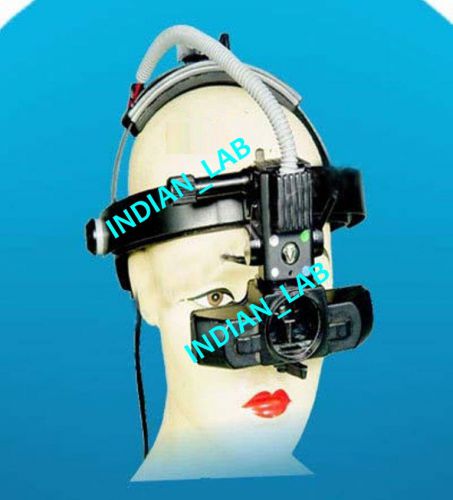

Indirect Ophthalmoscope Optometry Excellent Quality Free Shipping 120